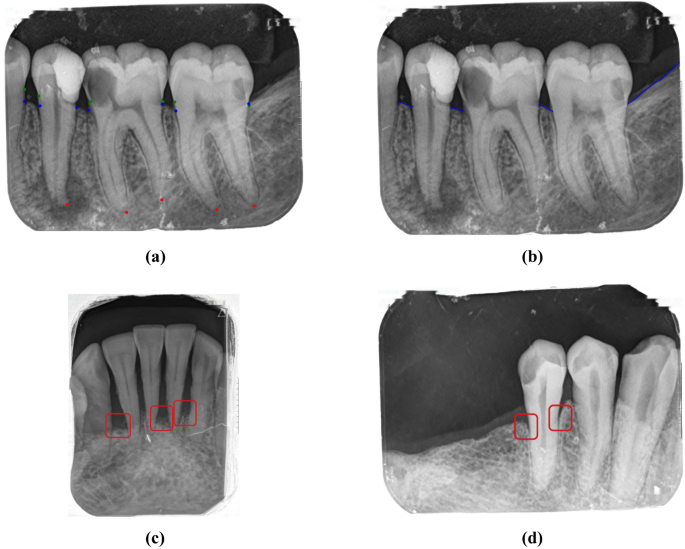

Overview of key features and case classifications used in alveolar bone loss pattern analysis. a Key points required for alveolar bone loss analysis; b Alveolar bone levels for pattern assessment; c Alveolar bone loss cases with horizontal pattern; d Alveolar bone loss cases with angular (vertical) pattern.

This reduction in bone height also causes changes in the alveolar crestal bone morphology. Understanding the nature of these alterations is essential for effective treatment planning. Radiologically, two main alveolar bone loss patterns could be identified as horizontal or angular (vertical) bone loss11. The horizontal pattern shows a uniform reduction in alveolar bone height around the teeth, as seen in Fig. 1c, while the vertical (angular) pattern shows an uneven reduction that creates an angular appearance12, as shown in Fig. 1d. Clinicians use radiographic analysis to differentiate between these two bone loss patterns, which would assist in treatment planning, especially for periodontal regenerative approaches.

Depending on the probing depths detected, for the sites with deep periodontal pockets, periapical radiographs are usually recommended, while for mild-moderate pocket depths, a bitewing radiograph could be applicable8. The identification of alveolar bone loss is critical in periodontal diagnosis, which would reflect as the clinical attachment loss9. Therefore, during radiological assessment, the extent of bone loss is assessed aligned with the long axis of the neighboring teeth, by evaluating the vertical distance between the cemento-enamel junction (CEJ) and the alveolar crest10. Figure 1a illustrates the key points used to assess alveolar bone loss on an intraoral periapical radiograph (IOPA).